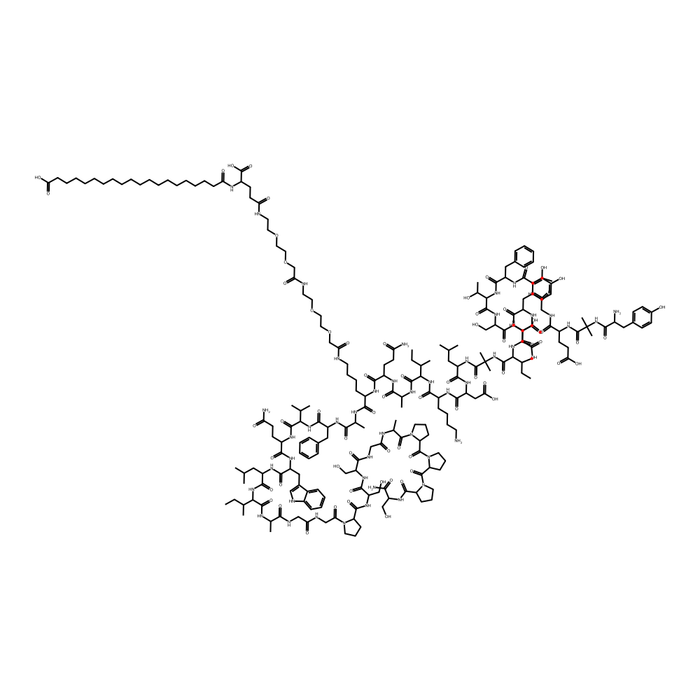

Tirzepatide

CAS: 2023788-19-2

Molecular Formula: C225H348N48O68

Molecular Weight: 4810.52